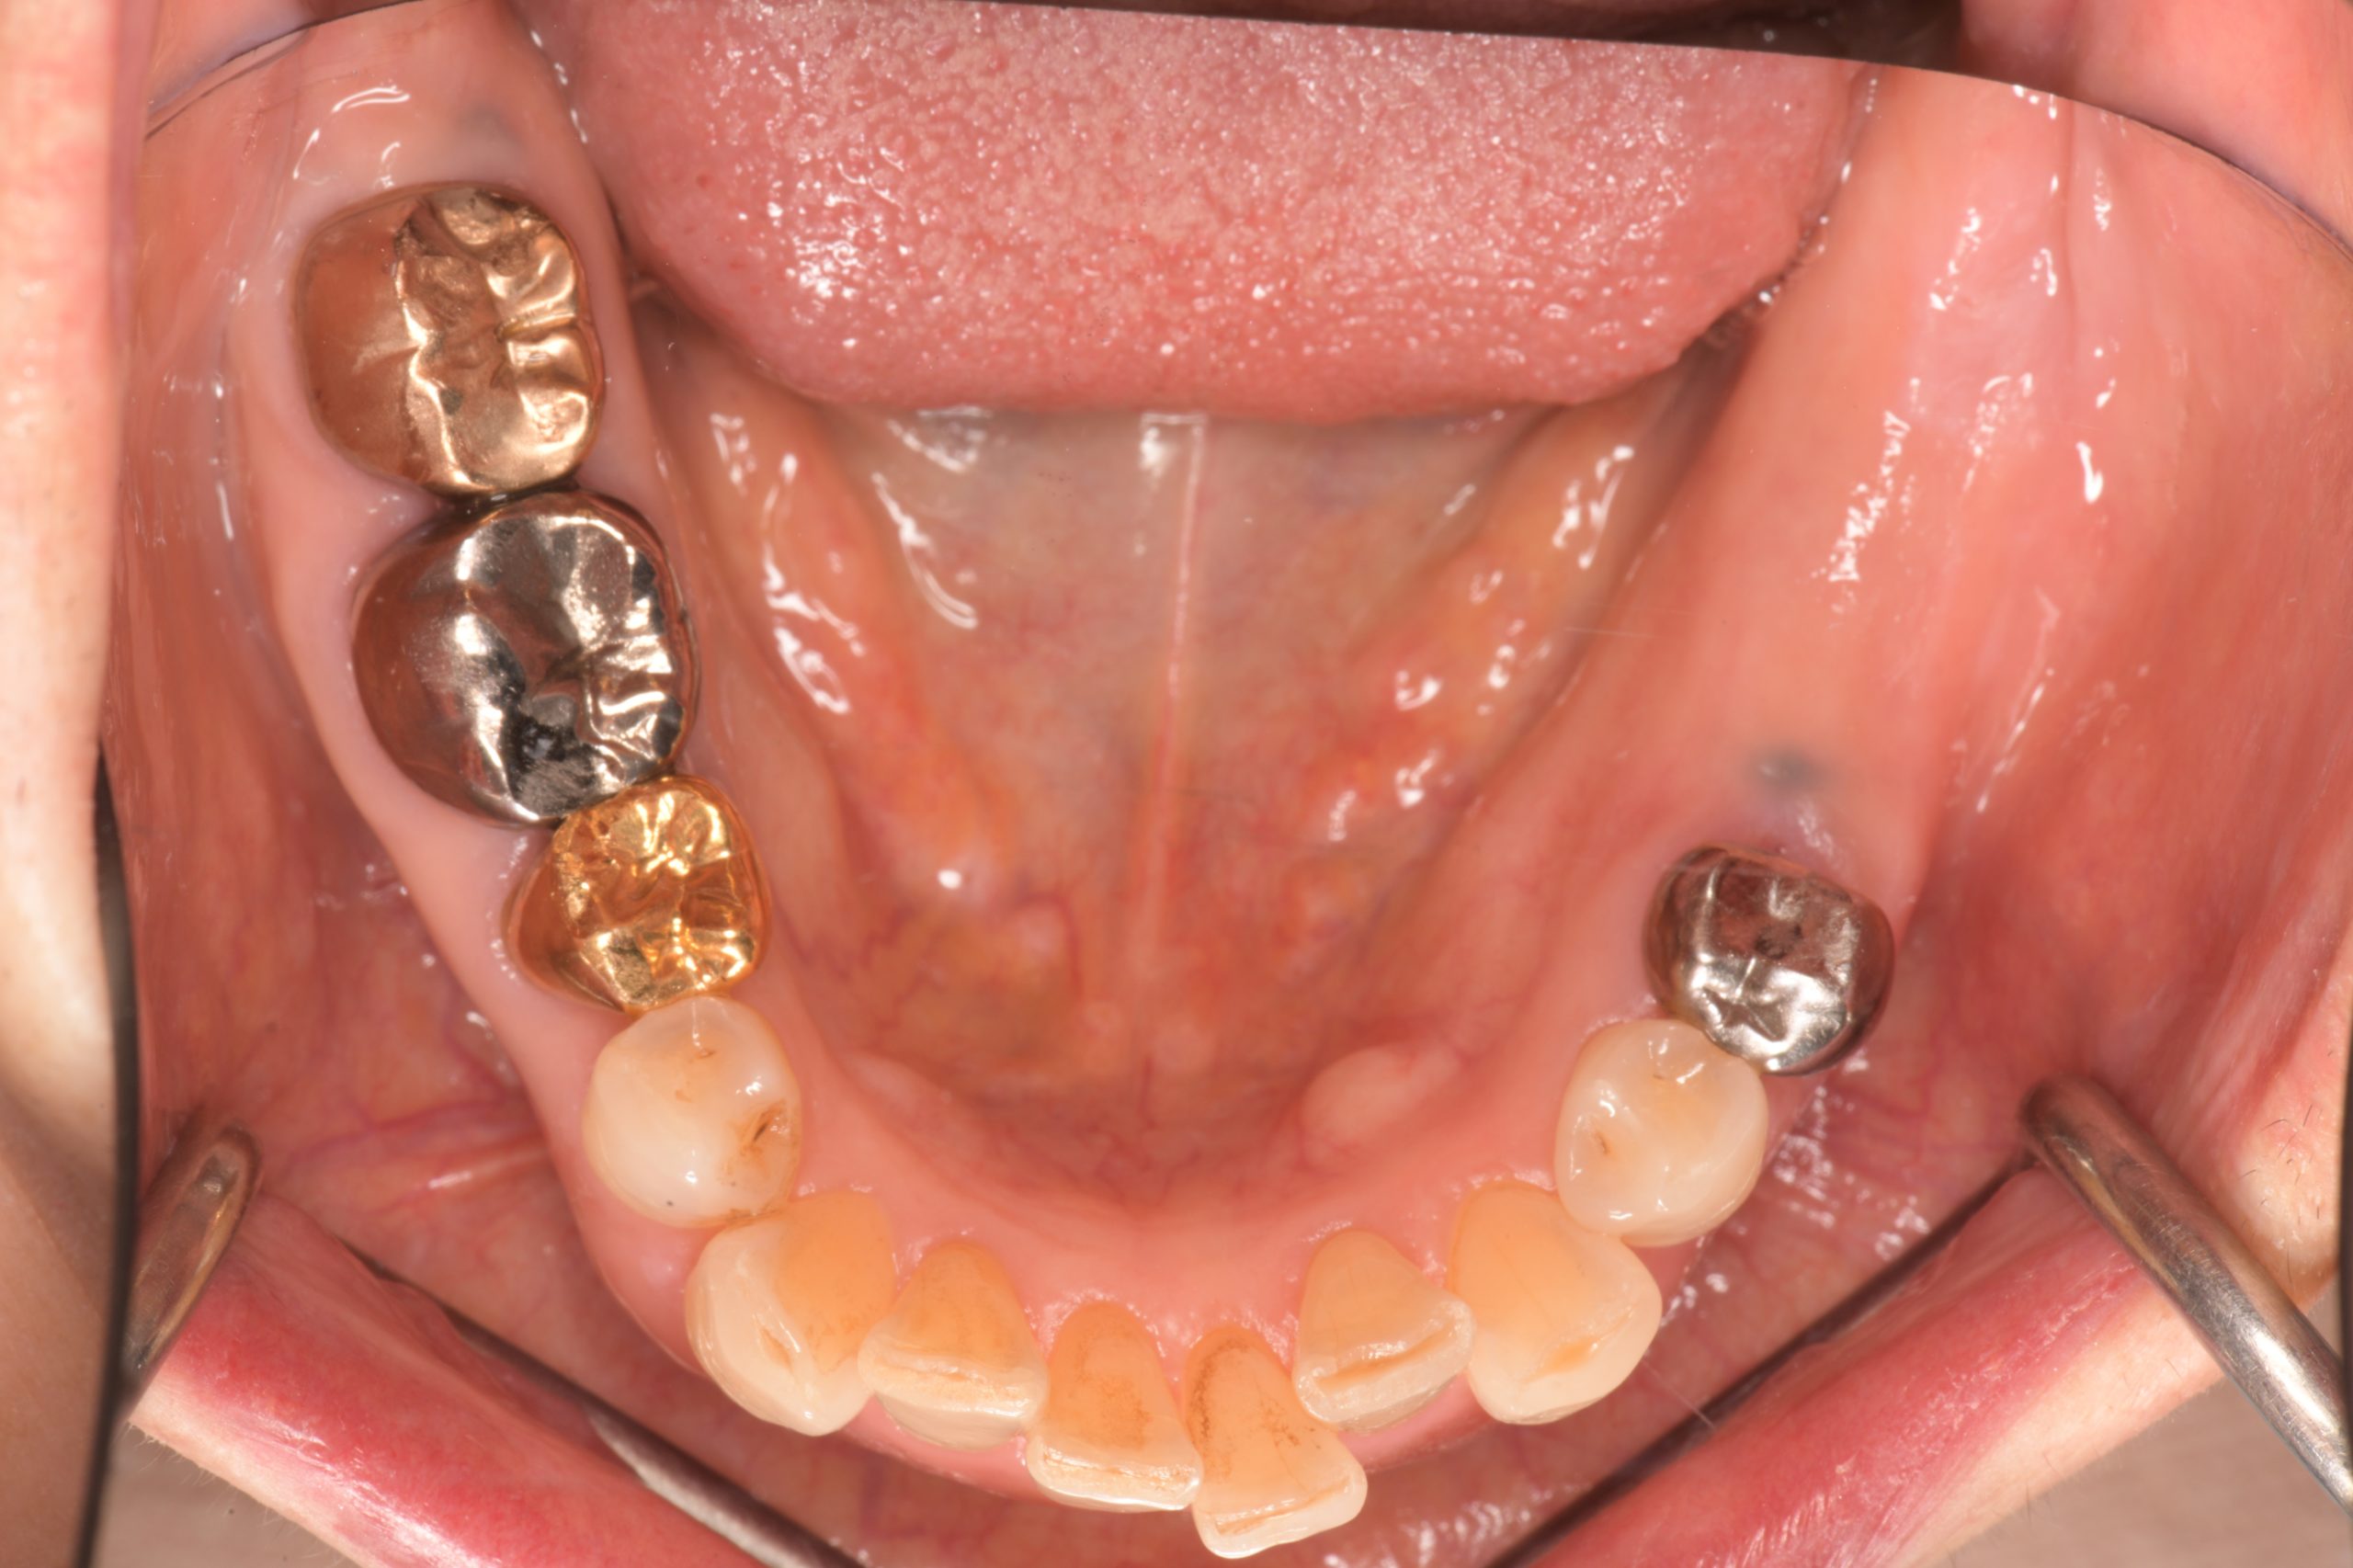

下顎臼歯部インプラント治療前

下顎臼歯部インプラント上部構造装着前

下顎インプラント治療完了